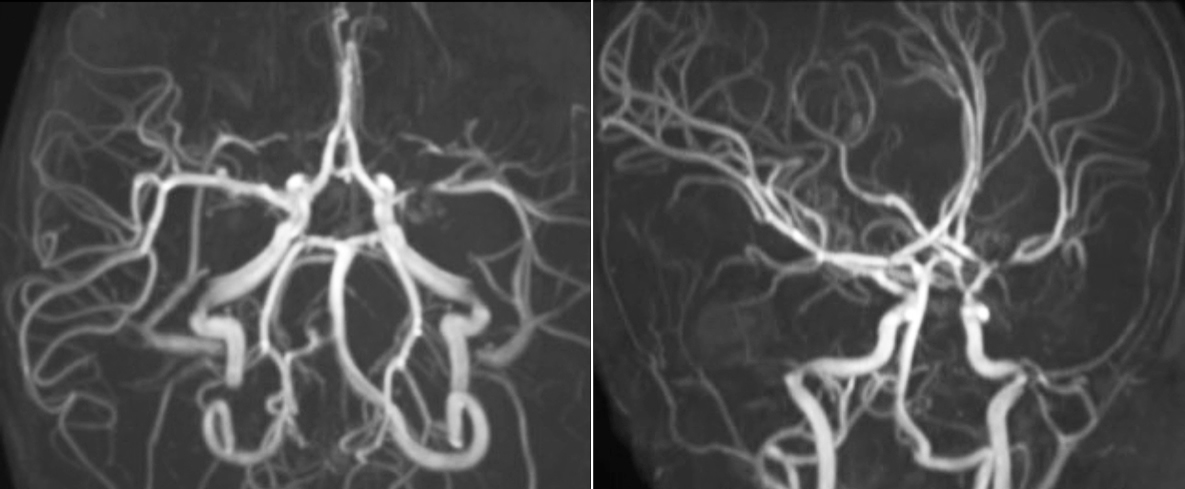

Pseudo-continuous arterial spin labeling (pCASL) was developed for brain perfusion imaging without contrast agent. “This is very desirable in pediatric patients where the general trend is to limit the administration of contrast,” says Dr. Miller. Growing confidence in specific applications “We built up confidence in pCASL by comparing it to contrast-based perfusion imaging. Once we had confidence that it was representing what the contrast perfusions were representing, we increased our diagnostic confidence by serial imaging in either the acute stage or the long term stages in a number of patients with arterial abnormalities.

Dr. Miller uses pCASL for all patients who present with chronic and acute cerebrovascular abnormalities such as acute stroke, as well as patients who present with signs of acute inflammation in the brain, and occasionally in patients with tumors, to assess the perfusion status of their tumor.

“In combination with diffusion weighted imaging, it can help give a more extended assessment of the degree of perfusion abnormality in a patient who is suffering acute ischemia. We have a number of patients who have chronic arterial insufficiency due to prior arterial abnormalities or acquired arterial abnormalities such as sickle cell disease or neurofibromatosis. Sometimes the child’s first manifestation of disease progression is a reduction in brain perfusion before stroke symptoms manifest clinically or in diffusion weighted imaging. We use pCASL to help delineate the perfusion abnormality.”

To other new users I would recommend to also start to interpret the pCASL images in comparison with other standard imaging – T2 and FLAIR and DWI – until the user gains confidence in interpreting these images by themselves.” “A powerful use of pCASL is in patients with chronic cerebrovascular stenosis, where clinicians desire information on how compensatory mechanisms of the brain are performing to enable perfusion to the brain. Often clinicians take into account how the compensatory mechanisms appear to help to provide adequate perfusion to the patient’s brain, and they may intervene surgically or make some other management decision.” “Another special application is the assessment of cerebrovascular reactivity with a Diamox perfusion exam, where we subtract two sets of pCASL images.”

“pCASL has now become more of a first-line scan for assessing perfusion for us, as opposed to DSC-based perfusion imaging with contrast agent. And in patients who were not planned to have contrast, we can perform pCASL for perfusion imaging without need to stop the exam, pull the patient out, and put in an IV. It also negates the postprocessing that’s necessary for dynamic susceptibility contrasts. And it allows us to repeat perfusion imaging in the same patient at the same imaging time, which is helpful in terms of patient motion, or in a situation where a scan needs to be done before pharmacological perfusion imaging.”